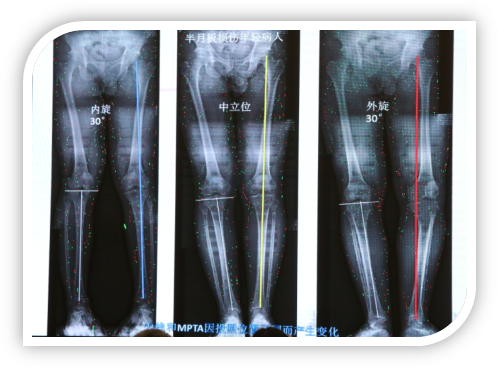

下图患者膝内翻并不严重,其内翻的表象主要来源于膝关节外旋,同时伴有屈曲畸形,当把膝关节放正以后,膝关节畸形并不严重。此病人照X光片,力线内移非常严重,但实际上这种病人伴有屈曲畸形和胫骨外旋。

image011.png

image012.png

下图患者因半月板损伤就诊,在中立位时力线通过膝关节中心,在膝关节内旋30°时力线外移,当膝关节外旋30°时力线内移,测出的MPDA是不同的,外旋下测出的MPDA是小的,完全可能因为照相的问题测出来的MPTA符合HTO的要求,但实际并非如此。

image013.png